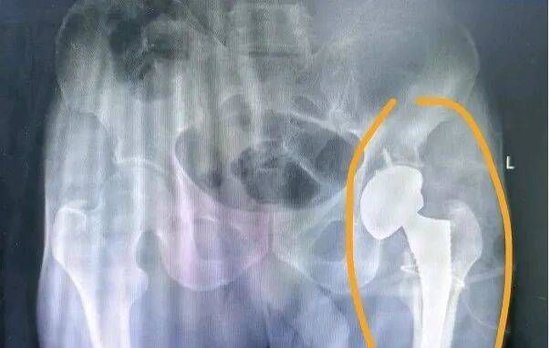

元旦期间,我院骨科医护团队成功为一名重症股骨颈骨折患者实施全髋关节置换手术。

患者杨先生摔伤致左侧股骨颈骨折,无法行走且剧痛难忍,家属专程送其来我院就诊。骨科邱岭副主任医师接诊后,评估病情并分析治疗方案,最终确定采用全髋关节置换手术。

1月1日上午9时,骨外科团队与麻醉科、手术室医护密切配合,顺利完成手术。此次手术的成功开展,彰显了我院骨外科团队的技术实力与责任担当,更凝聚起多学科协作的坚实力量,我院将继续坚守初心,为群众健康保驾护航。